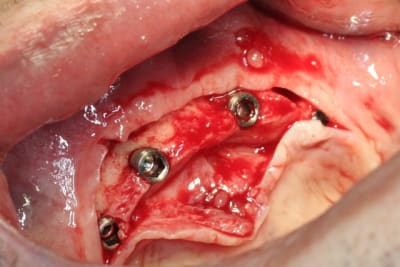

barre pour stabilisation du complet bas...;-)

le patient, niveau budget pouvait se permettre mieux...on aurait pu faire sans problème un all on six (ou plus) transvissé...si son état de santé avait été meilleur...pas très grave...mais son Parkinson lui complique l'hygiène buccale...alors passer des brossettes loin au fond...là au moins son épouse pourra l'aider...çà sera pas trop compliqué...et au niveau confort, c'est quand même pas mal...

mais le ptit plus de cette intervention...c'est pas les mêmes implants que d'hab...c'est des drive implant...pas mal du tout...du moins pour la chir...

forets super...avec butées clipsables (très pratique et sécurisant), super stab primaire...très sympa...

ah, celle là, je l'attendais...c'est court parce qu'il y a, après étude du scan...un gros, très gros canal incisif qui passe juste dessous...et qui donne un foramen mentonnier dans la zone antérieur...bien identifié...du genre à contenir un faisceau sensitif pour le menton et la partie médiane de la lèvre...tu vois ce que je veux dire...???

pour ce cas, j'ai posé en 34 et 44 des 4x8...et pour 32 et 42 des 4x10...

pour répondre à une autre de tes questions..."pourquoi pas les expanseurs"...simple...la bourde...l'assistante qui oublie de les mettre à stériliser...mais bon y manque pas grand chose en vestibulaire...et c'est aussi pourquoi j'ai mis des 4mm en 34 et 44...à l'origine je voulais mettre des 5mm...